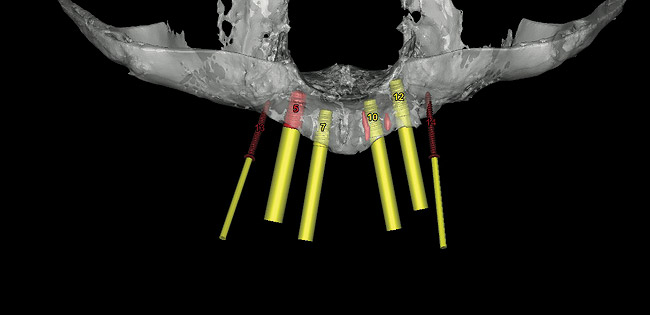

Figure 8  Virtual implant placement and fixation screws.

Figure 8

These patients were tested for two different treatment options; either a bar-supported overdenture requiring four implants in the first premolar area or anterior to the bicuspids, or a "simple fixed prosthesis" anchored by six implants placed bilaterally from first-molar-to-first-molar regions. When a flapless, guided surgery was contemplated, the investigators determined that based on the available maxillary bone, 70% of patients (28 implants) could undergo this treatment modality. Of the 40 patients, 15% could not have any implants placed due to inadequate bone height and width. For "simple fixed prostheses," only 30% (72 implants) of patients presented with adequate bone dimensions permitting a flapless guided placement of six maxillary implants placed symmetrically around their arch in a flapless manner. For the fixed treatment, 18% of patients could not have any implants placed due in insufficient bone dimensions. The authors concluded that advertisement of computer-guided, flapless solutions are "euphoric," and tend to overlook patients' individual oral and anatomic conditions. They felt that guided surgery does provide better control of implant placement leading to higher predictability of treatment outcomes. In a study where the accuracy of virtually placed implants and actual positions in a cadaver model were compared, Petterson et al7 found significant differences related to deviations in hex, apex, and depth of the two placements. Without the preparedness to temper treatment expectations or plan on delivery of the pre-fabricated "final" prosthesis immediately after surgery, these types of studies should lead clinicians to proceed with caution in these procedures. The efficacy of an open approach, one requiring a mucoperiosteal flap, may be improved upon with a guided approach in cases where severe ridge-resorption is treated, and may be more predictably handled using this technology. A bone-supported template, affixed to the alveolar ridge with fixation screws, can be fabricated with numerous software package and stereolithography (Figure 8 and Figure 9). A full-thickness flap is elevated, exposing the resorbed alveolar ridge (Figure 10). Using osseous fixation screws, the template is stabilized to the ridge, preventing any movement during osteotomy preparation (Figure 11). Using a sleeve-in-sleeve, manufacturer-specific surgical armamentarium, implants can be placed in the optimal positions, where the maximum amount of initial bone to implant contact is achieved. The anticipated bone augmentation procedures can then be performed, which is not possible with a closed procedure (Figure 12). The flaps are subsequently closed, allowing for the patient to wear any transitional, soft-relined denture. The surgical guide can also serve an important function at the time of implant uncovering. The location of the implants beneath the healed mucosa can be determined by seating the guide and sounding with a 30-gauge anesthetic needle. Using a tissue punch, the implants can be uncovered without flap elevation; the cover screws can be removed and the appropriately sized healing abutments can be placed (Figure 13). From this point forward, traditional prosthetic steps are followed to fabricate an implant-supported/retained overdenture.